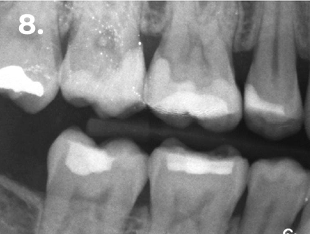

Paciente que acude a consulta refiriendo molestias en la zona del primer cuadrante. La exploración clínica y radiográfica reveló la presencia de una caries profunda distal, estableciéndose el diagnóstico pulpar de pulpitis reversible. Con el objetivo de lograr un adecuado punto de contacto tanto mesial como distal, se procedió a la eliminación completa de la restauración existente. El procedimiento se realizó bajo aislamiento absoluto, utilizando para el encofrado el sistema de matrices seccionales HALO. En la imagen clínica y radiográfica final se observan perfiles de emergencia bien conformados, convexos, así como puntos de contacto adecuados.

Fig. 8 Radiografía de aleta de mordida final